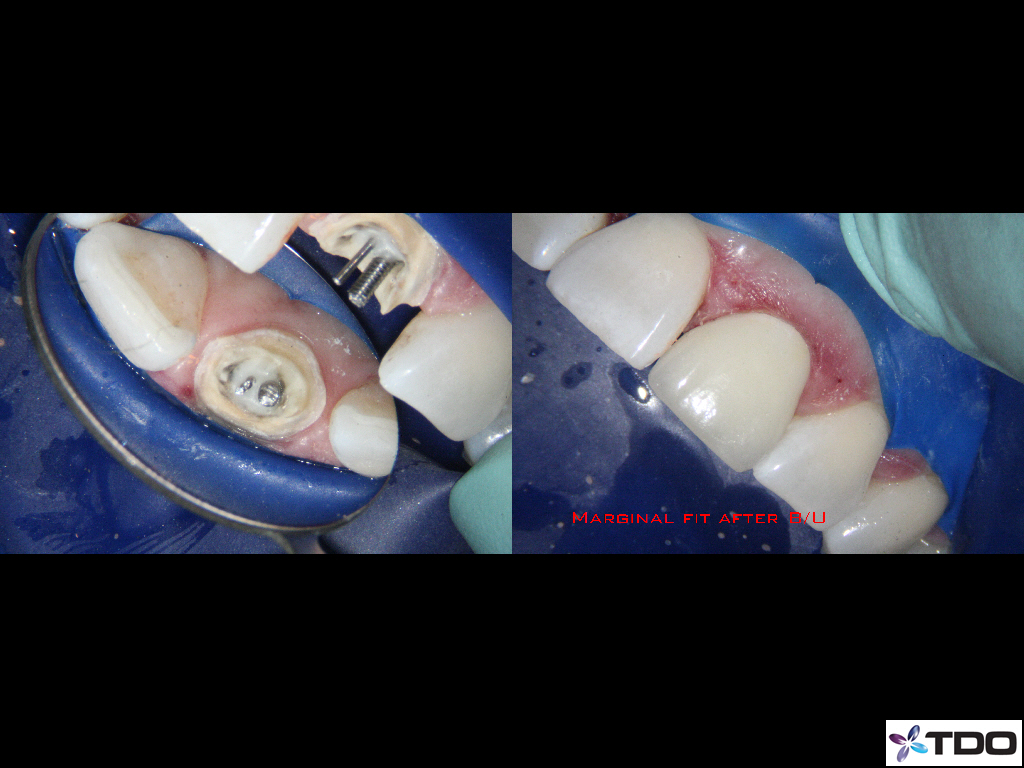

This patient fractured her front tooth.  The crown was only 2 years old.  Extraction and implant placement was recommended.  It would have been a challenging case esthetically.  We were able to retreat the contaminated root canal.  Posts were placed for reinforcement.  We were able to use the existing crown by retrofitting it.  We managed the occlusion to mitigate the risk of future fracture.